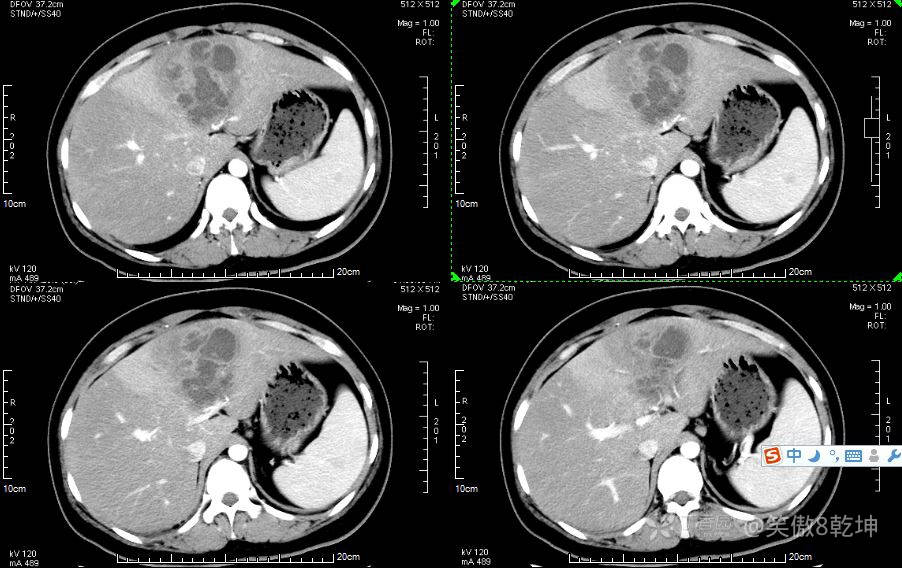

诊断似乎倾向于肝脓肿了,与患者或家属沟通后完善上腹部强化CT:

证实为肝脓肿,至此,诊断思路似乎清晰起来,患者血糖的升高使得微小血管容易出现循环障碍,同时白细胞的吞噬能力及抗感染能力下降,所有易出现感染性疾病。而肝脓肿通常不容易早期发现。患者的年龄同时让临床医生不容易想到此诊断。